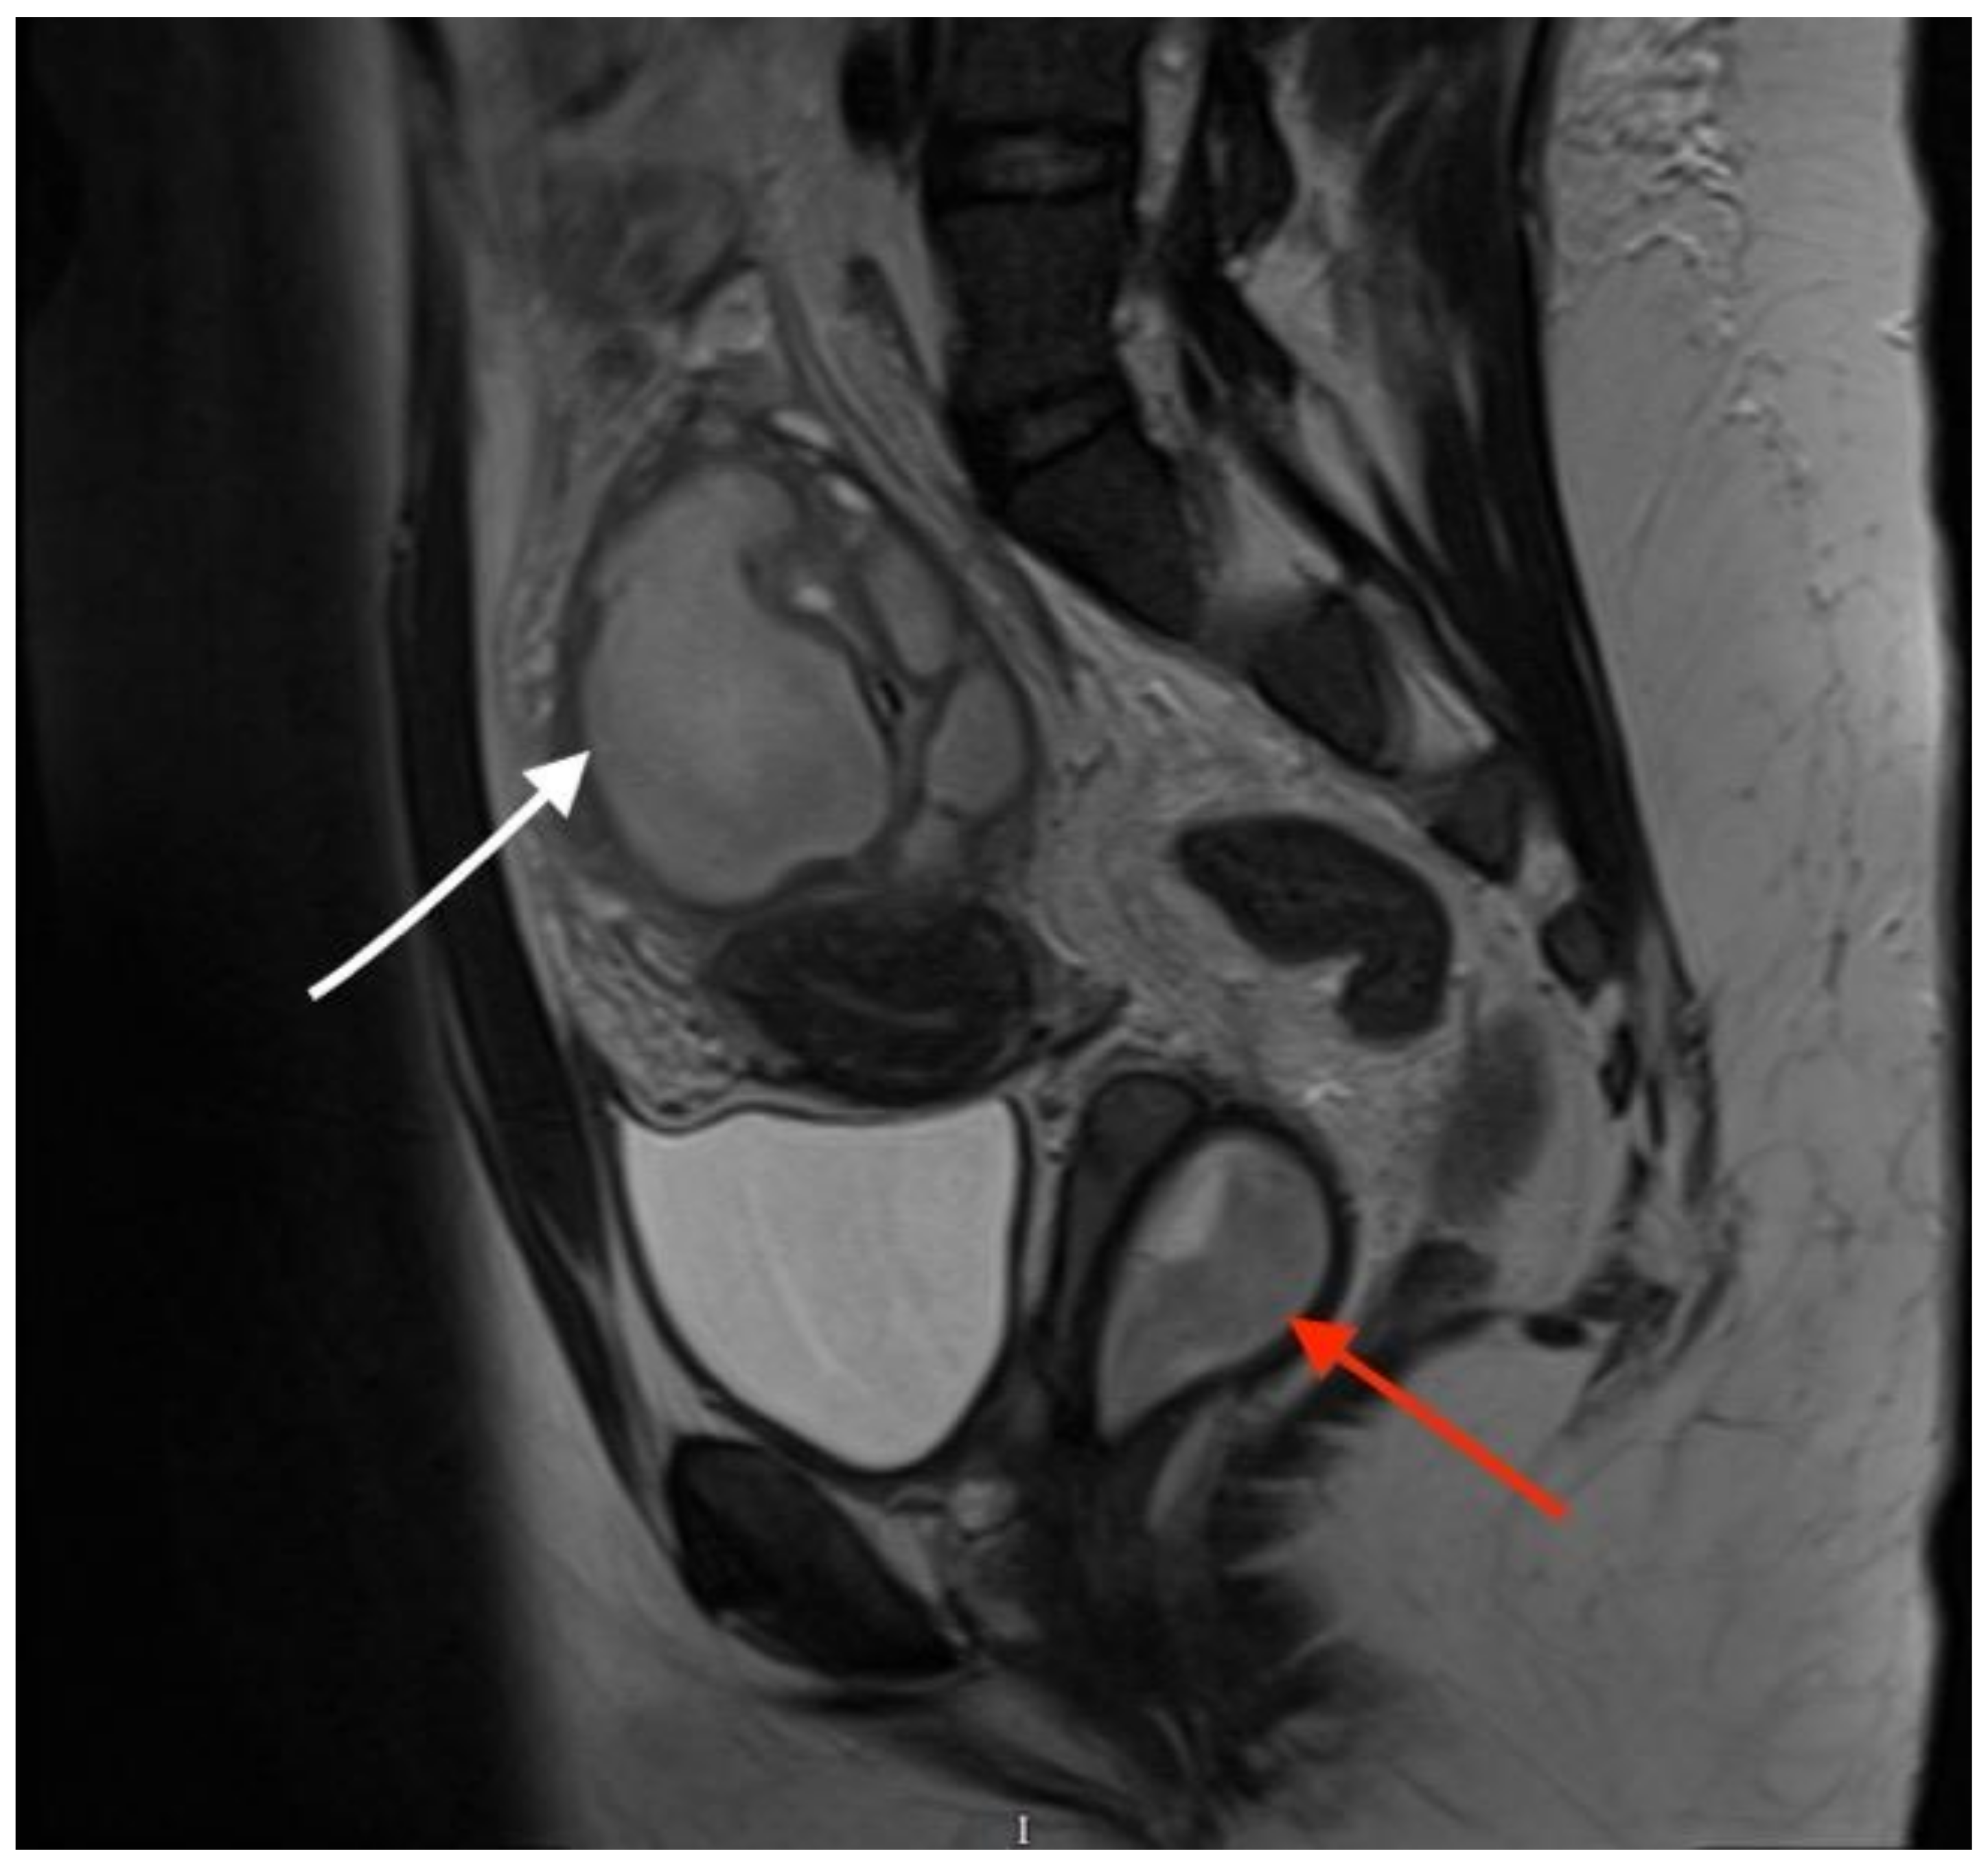

Sagittal T2-weighted MR image showing a vaginal septum with a haematopyocolpos of the obstructed hemivagina and a tubo-ovarian abscess (red arrow indicates the obstructed haematopyocolpos, and white arrow shows the tubo-ovarian abscess). The presence of gas and fluid within the lumen was indicative of a concurrent infection. The patient was initially treated with intravenous antibiotics after the provisional diagnosis of PID. After three days of treatment, she continued to have episodes of pyrexia, the CRP level remained high (242 mg/L) and there were persistently high WCC (16.5 × 109/L) and platelet quantities (500 × 109/L). On the third day after admission, the diagnosis of OHVIRA syndrome was finalised, and the decision was taken to take the patient for surgical intervention to drain the haematocolpos and perform a laparoscopic exploration, to which the patient consented. The next day, the patient underwent an examination under anaesthesia, vaginal septectomy and drainage of the haematopyocolpos. Intraoperative hysteroscopy confirmed the presence of a uterus didelphys bicollis. The cervix of the affected cavity was dilated to encourage continuous drainage. Subsequently, during the laparoscopy, significant pelvic adhesions were noted, involving the bowel being adherent to the uterus, and a large right-sided tubo-ovarian abscess. Laparoscopic adhesiolysis was performed, as well as the drainage of the abscess. The pelvic drain was left in situ at the end of the procedure. She remained an inpatient for four days after surgery. The drain was removed three days after the operation. She was continued on intravenous antibiotics for a further three days before they were converted to oral medication. She no longer had a post-operative spiking temperature, and her pulse normalised two days after the operation. Her CRP dropped to 51 mg/L and WCC to 9.5 × 109/L on the day of discharge. She was followed up in the Gynaecology Clinic with repeat imaging that confirmed the resolution of the tubo-ovarian abscess. She was carefully debriefed about the implications of having uterus didelphys and a single kidney in pregnancy and was further signposted to written information provided by the British Society of Paediatric and Adolescent Gynaecology.